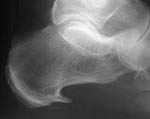

Heel spur is technically a "medial subcalcaneal exostosis at the inner tubercle of the os calcis" This means a protuberance of the heel bone where it attaches to the plantar fascia (see x-ray illustration).

If this finding is present with pain overlying the area of the spur, the patient is said to have "heel spur syndrome". Since the plantar fascia connects to the heel spur, it is clear why "plantar fasciitis" and "heel spur" are often used interchangeably.